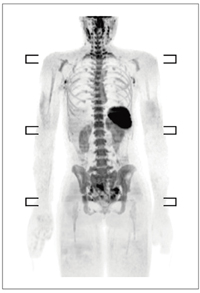

さらにデジタルコイルでは,SENSEによるSNR減衰も補填する。したがって,拡散強調画像において5倍速などの大きなSENSE factorを設定でき,広範囲でも歪みのない検査を行える(図5)。

図5 デジタルコイルが可能にするSNRの高いDWIBS (スキャンタイム 2:09/station,1.5T)

図5 デジタルコイルが可能にするSNRの高いDWIBS

(スキャンタイム 2:09/station,1.5T)